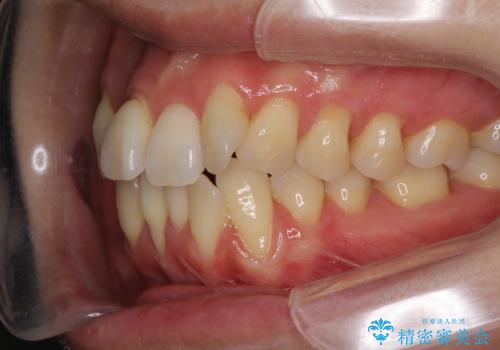

通常であれば、上下顎左右小臼歯各1歯の合計4本を抜歯しますが、歯肉退縮の著しい下顎前歯を抜歯して欲しいという患者様の強い希望により、上顎のみ左右小臼歯2歯を、下顎は前歯を1歯を抜歯することとしました。

抜歯する歯を変更したため奥歯の咬合はアンバランスとなりましたが、前歯は綺麗に整い、歯肉退縮も回避できました。